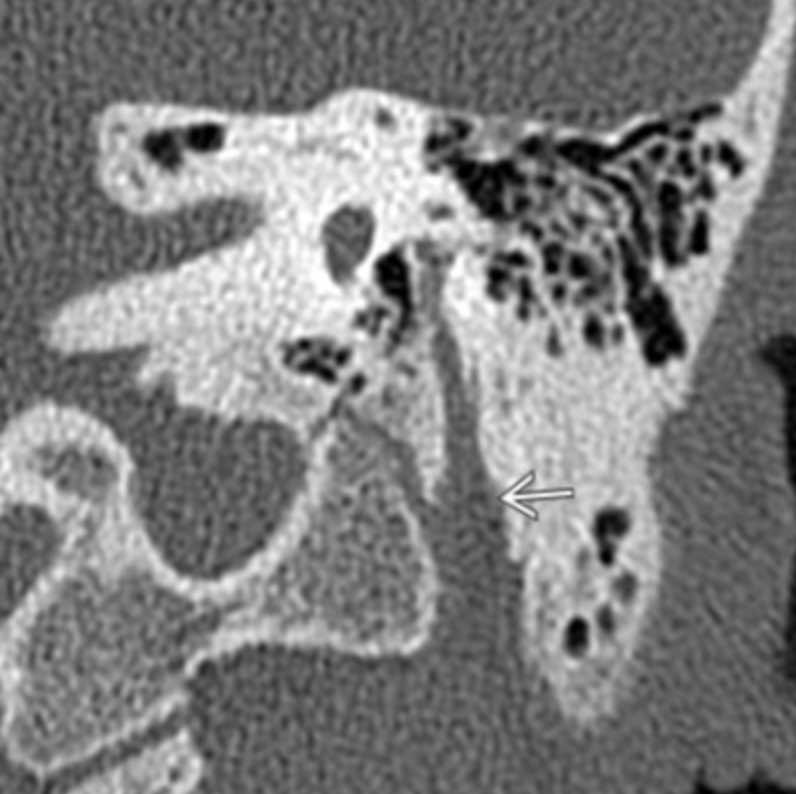

Sphenopalatine Foramen

• #1 in image to the right

• Allows passage of nasal cavity and pterygopalatine fossa

• Transmits

• Sphenopalatine artery & vein

• Nasopalatine nerve

• Posterior superior nasal nerves

• Clinical relevance

• Because nerves travel through here, it allows a possible passageway for peri-neural spread of malignancy from the nasal cavity to deeper structures

• Juvenile Angiofibromas